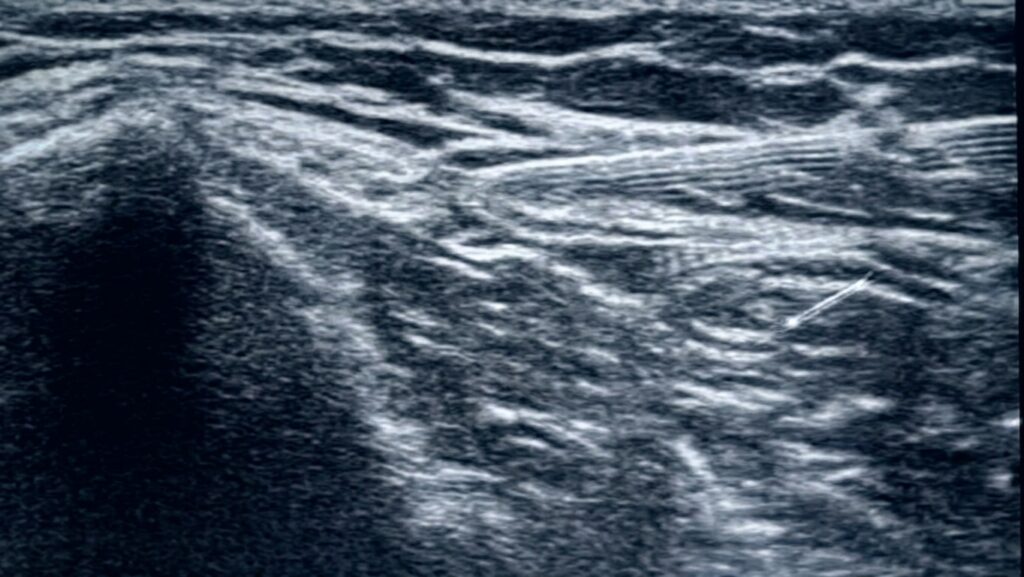

医師の手探りではなく、最新の超音波エコー装置を使って、皮膚の下の「筋膜が白く癒着している部分(痛みの原因)」をミリ単位で正確に見つけ出します。

ハイドロリリース(Hydro Release)は、超音波エコーでリアルタイムに筋膜の癒着を確認しながら、生理食塩水をピンポイントで注射し、水の圧力で癒着を物理的に剥がす治療法です。当院では局所麻酔薬を使用しない「純粋生食プロトコル」を採用しています。薬剤アレルギーのリスクをほぼゼロにし、「純粋に筋膜を機械的に剥がす効果」のみをお届けします。